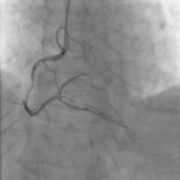

Refer to caption

(a) (a1)

(b) (a2)

(c) (a3)

(d) (a4)

(e) (b1)

(f) (b2)

(g) (b3)

(h) (b4)

(i) (c1)

(j) (c2)

(k) (c3)

(l) (c4)

Figure 7: Experimental results of automatic stenosis detection. (a) Xiao’s method. (b) The proposed method. (c) Ground truth.

Study of automatic stenosis detection

To further test the effectiveness of the proposed automatic method, we adopt Xiao’s method xiaoAutomaticVasculatureIdentification2013 , i.e., replace our tracking method and method of diameter measurement with hers in automatic stenosis detection, as a baseline. Fig. 7 shows the comparison of automatic stenosis detection between the proposed method and Xiao’s method. We observe that our method can detect stenoses more accurately and make fewer mistakes. This is because we have a better tracking method and more precise diameter measurement, which will be discussed later.

Table. 1 shows that the results of the proposed method are better than Xiao’s method on all metrics. And the proposed method(τ_3=0.8subscript𝜏_30.8\tau_{\_}3=0.8) improves the sensitivity while only sacrificing a little precision compared to (τ_3=0.5subscript𝜏_30.5\tau_{\_}3=0.5). As we focus more on detecting all the stenoses, it is accepted to make some incorrect predictions.